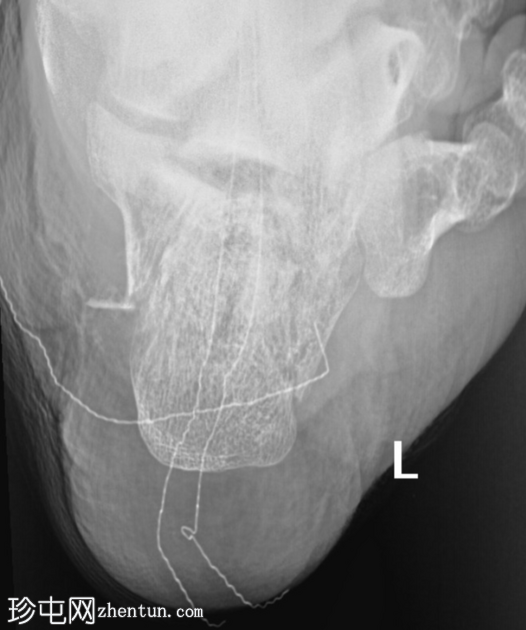

轴位片

关节内粉碎性跟骨骨折(侧位/轴位片)。

未见其他骨折或下胫腓联合损伤。

绷带中的放射性标记物造成伪影。